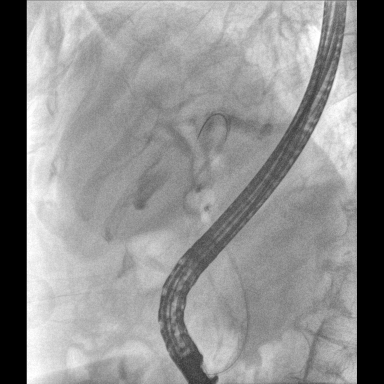

具備血管造影及數(shù)字減影(DSA)、路徑圖(Road-map)、透視、攝影等功能。 廣泛適用于介入科、血管外科、腫瘤科、消化內(nèi)科及骨科等多個(gè)臨床科室,典型應(yīng)用包括:TACE(肝腫瘤栓塞與化療灌注術(shù))、心臟起搏器置入術(shù)、四肢動(dòng)脈造影術(shù)、下肢靜脈濾器置入術(shù)、ERCP(經(jīng)內(nèi)鏡逆行胰膽管造影術(shù))等。

核心DSA軟件可實(shí)時(shí)生成高清血管影像,結(jié)合路徑圖功能,在手術(shù)中為醫(yī)生提供血管導(dǎo)航。

設(shè)備搭載自主研發(fā)的大功率高壓發(fā)生器、高熱容球管與大尺寸平板探測(cè)器,配合先進(jìn)圖像處理算法及高效冷卻循環(huán)系統(tǒng),能夠在長(zhǎng)時(shí)間手術(shù)過(guò)程中持續(xù)輸出高清圖像并保持幀率穩(wěn)定。